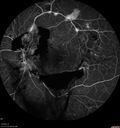

44 year old man About 2 months ago, the patient went to the beach with his family and noticed a hair in the eye sight in the left eye.  He was trying to rinse it out and saw that there was something not right.  He googled the problem and there was something about a floater and not being a big deal.  His vision was pretty good.  He was not getting regular eye examinations.  He did get checked in 2015 and got new glasses.  He had not been back since then for the last 5 years except for glasses. Last week the vision in the left eye got bad.  The vision in the right eye is fine.   VA OD: sc20/40 PH20/25 NscJ2 VA OS: sc20/63-2 PH20/32-1 NscJ1 IOP: TP: OD:17 OS:19

Proliferative Diabetic Retinopathy and vitreous hemorrhage left eye330 views44 year old man with type II diabetes for 14 years and no eye examinations in the last 5 years. VA 20/40 right eye and 20/60 left eye. Vision loss has been for about a week in the left eye.00000

44 year old man About 2 months ago, the patient went to the beach with his family and noticed a hair in the eye sight in the left eye.  He was trying to rinse it out and saw that there was something not right.  He googled the problem and there was something about a floater and not being a big deal.  His vision was pretty good.  He was not getting regular eye examinations.  He did get checked in 2015 and got new glasses.  He had not been back since then for the last 5 years except for glasses. Last week the vision in the left eye got bad.  The vision in the right eye is fine.   VA OD: sc20/40 PH20/25 NscJ2 VA OS: sc20/63-2 PH20/32-1 NscJ1 IOP: TP: OD:17 OS:19Â